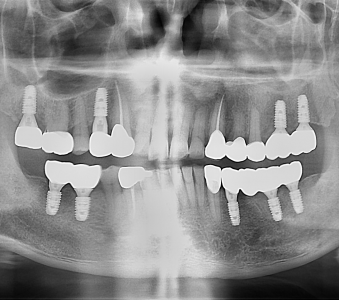

오스템 임플란트 프리미엄 BA 등급 사용

같은 오스템이라도 등급이 다릅니다. 더 빠른 골유착을 위해 프리미엄 등급을 사용합니다.

정확성 높은 치료의 시작 디지털 정밀진단 시스템

3D 디지털 데이터 기반으로 정확성 높고 정교한 치료가 가능합니다.

결과로 증명합니다.

국제모아치과의

실제 임상 증례